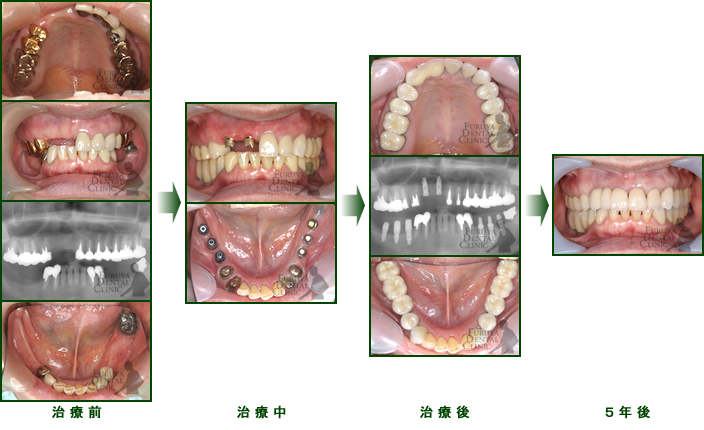

60代 女性

不適合な義歯を長期に使用していたため、かみ合わせが崩壊し、歯周病、虫歯も重度に進行していました。

時間をかけて虫歯、歯周病を手術段階まで治療、かみ合わせの再構築にインプラントを部分に分けて施術しました。

審美的にも20代の自身の口腔内以上に抗年齢を再現できたと思います。